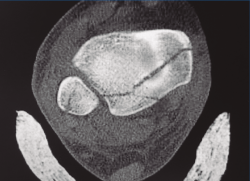

Indicado en los casos en los que la fractura de MP se extiende medialmente o presenta 2 fragmentos, uno posterolateral y otro posteromedial (fractura de tipo II de Haraguchi o de tipo 3 de Bartoníček). El paciente se coloca en decúbito prono. La incisión se realiza entre el maléolo interno y el tendón de Aquiles. Se secciona la fascia y se accede al paquete vasculonervioso y a los tendones flexores. Se puede acceder al MP a través de ambos lados del paquete. O bien desde un abordaje entre el tibial posterior y el flexor digitorum longus (FDL) o bien desde un abordaje más posterior, entre el paquete vasculonervioso y el FHL. El fragmento se moviliza y se reduce de forma provisional con agujas de Kirschner y definitivamente mediante tornillos o placa de soporte (Figura 3). La reducción de la fractura se comprueba mediante la visualización directa del ápex de la fractura y mediante control radioscópico. Hay que llevar sumo cuidado para proteger el paquete durante todo el procedimiento.

Figura 3. Imagen intraoperatoria de una fractura de tipo II de Haraguchi y de tipo 3 de Bartoníček a través de abordaje posteromedial.